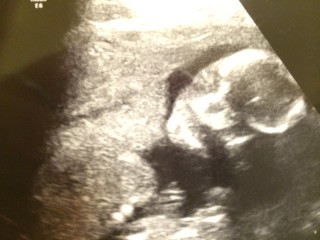

性別はまだはっきりしませんが、三週間前のエコーでは全く動いてくれなかったのが、今回はお口もあむあむ、足もバタバタ動いてくれてとっても幸せでした

性別は、まだ確定とまではいきませんが…

おそらく、男の子みたいです。